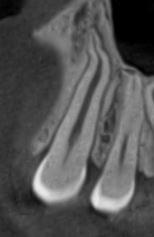

Зуб — це не просто монолітний об'єкт, а складна система мікроканалів. На плоскому 2D-знімку вони часто перекривають один одного, створюючи ілюзію простої анатомії.

Непомічений канал — це джерело майбутньої інфекції та причина «загадкового» болю після лікування. Завдяки високій роздільній здатності обладнання MyRay, лікар бачить кожен мікронний канал ще до того, як візьме до рук інструмент.